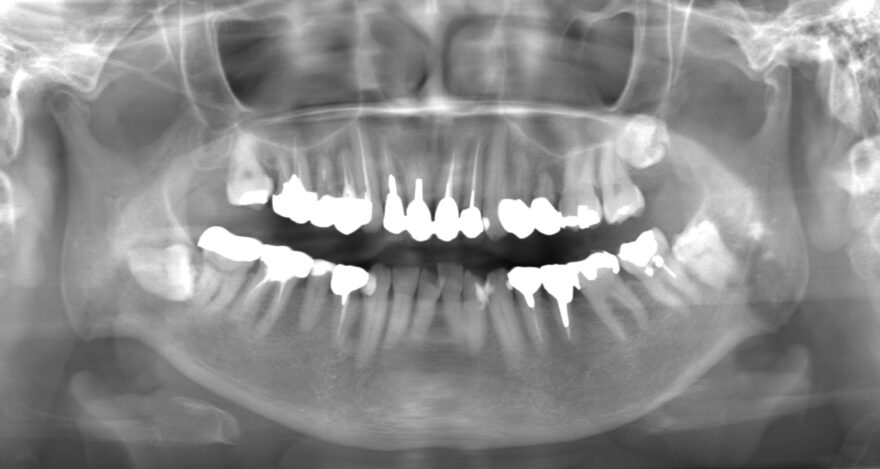

初診時のレントゲン写真